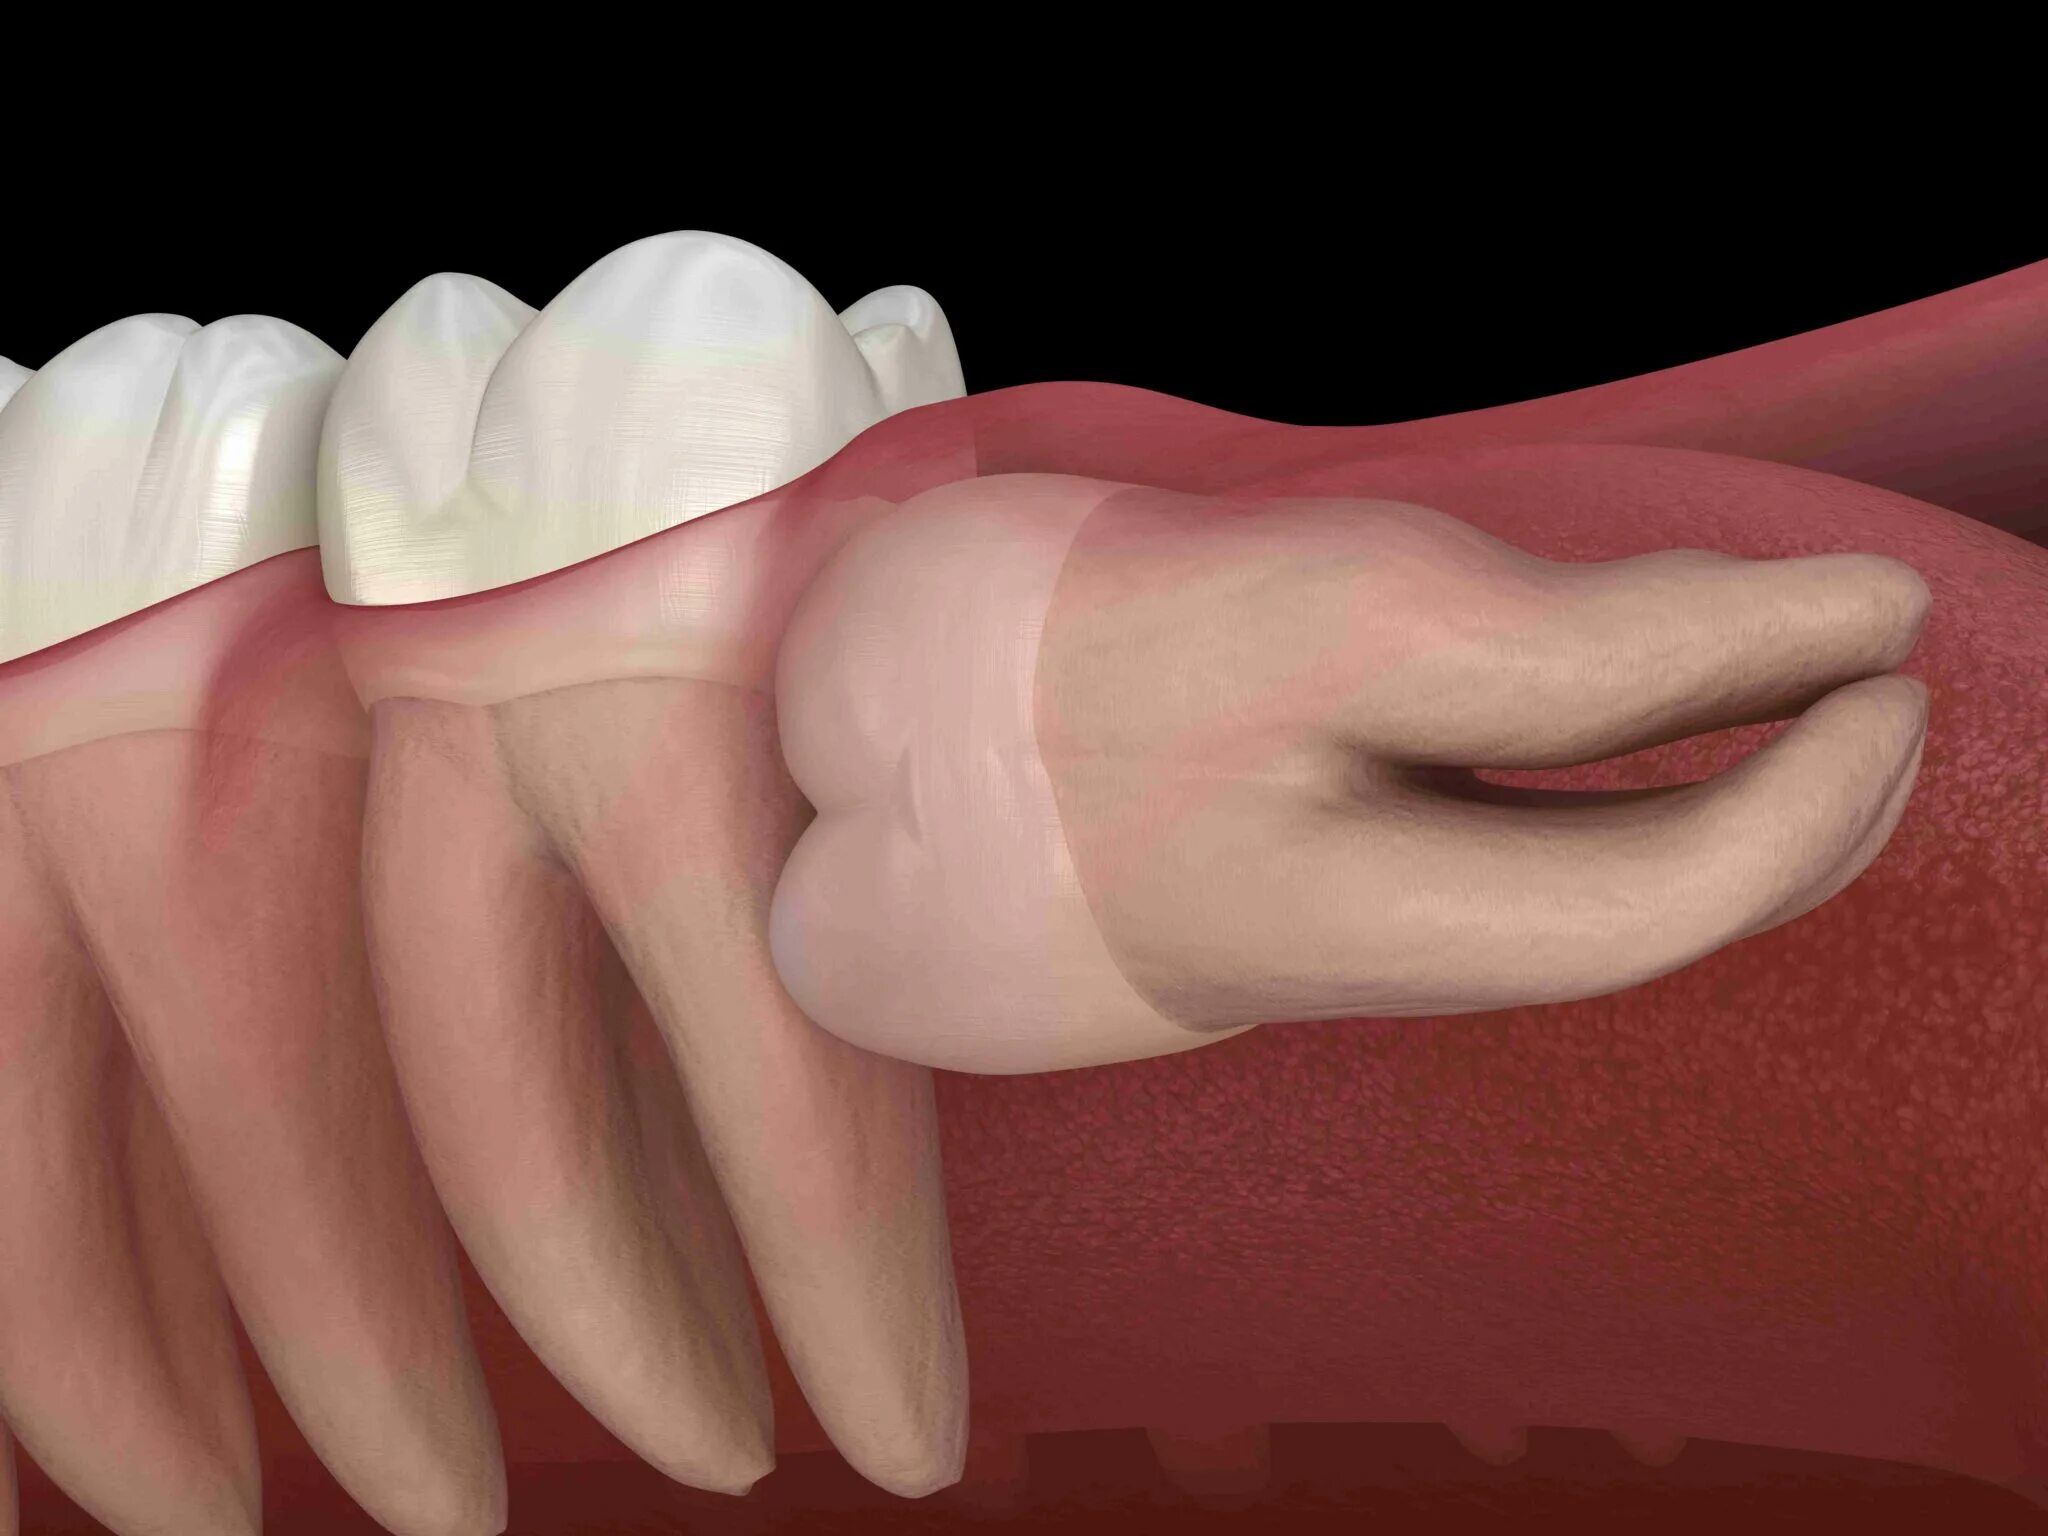

Зуб дистопирован